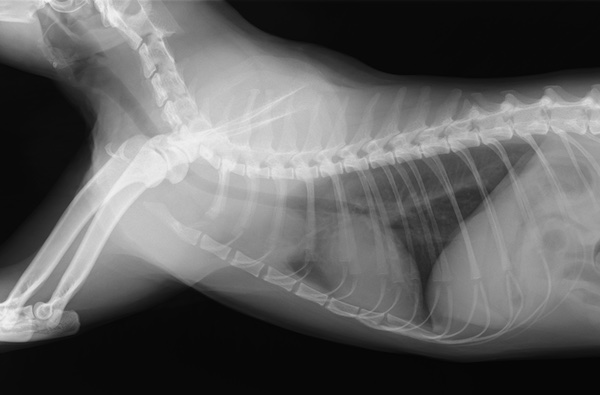

レントゲン検査にて胸の中にシコリを偶然発見しました。。

実は予想外の結果で、こうなると唾液腺嚢腫以外の可能性を考える必要があります。後日、当院にて全身麻酔にてCT撮影を実施しました。

結果、前縦隔と呼ばれる胸の中の空間に、女性の拳大の腫瘤病変を発見し、細胞診を行って得られた病名は「胸腺腫」でした。